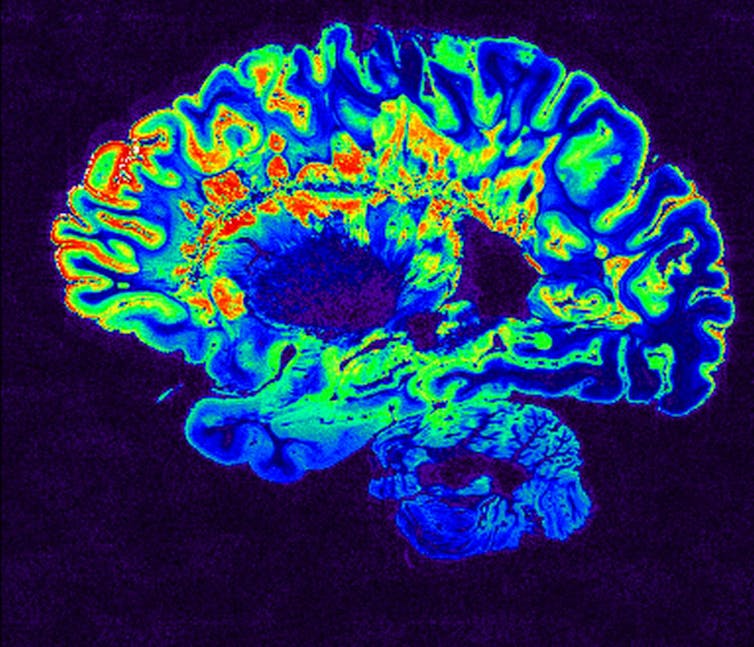

One way of finding out more is to take a look inside patients’ heads using brain-imaging techniques, such as MRI. So far, brain imaging has revealed a pattern of previously unseen findings, but its still very early days for using it in this pandemic.

In one study, patterns found included signs of inflammation and a shower of small spots of bleeding, often in the deepest parts of the brain. Some of these findings are similar to those seen in divers or in altitude sickness. They might represent the profound lack of oxygen being delivered to the brain in some patients with COVID-19 – but we are only starting to understand the full scope of the brain’s involvement in the disease. Brain-imaging and postmortem studies for those killed by COVID-19 have been limited to date.